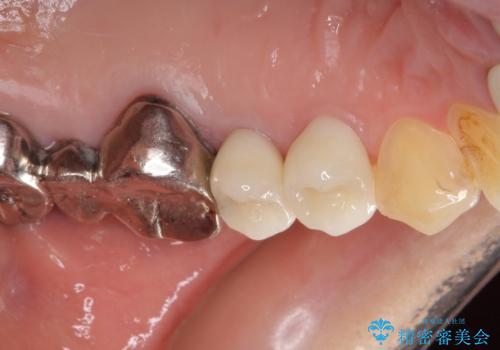

- 歯肉が退縮したためにクラウンの縁や歯根が見えてしまっていることを気にして来院された患者様です。

仮歯に変えた後にオールセラミッククラウンにて補綴することとしました。

強い咬合力や磨きすぎなどにより、歯根が見えてしまったり、金属の縁が見えてしまったりし、審美障害を引き起こすことがあります。

歯根が変色してしまうと、歯肉越しに歯根の黒い色が透けてしまうことがあり、この点についてはどうにも施しようがないため、患者様には事前のご理解いただきました。

治療前と比べてとても自然な前歯となり、患者様には大変満足していただきました。